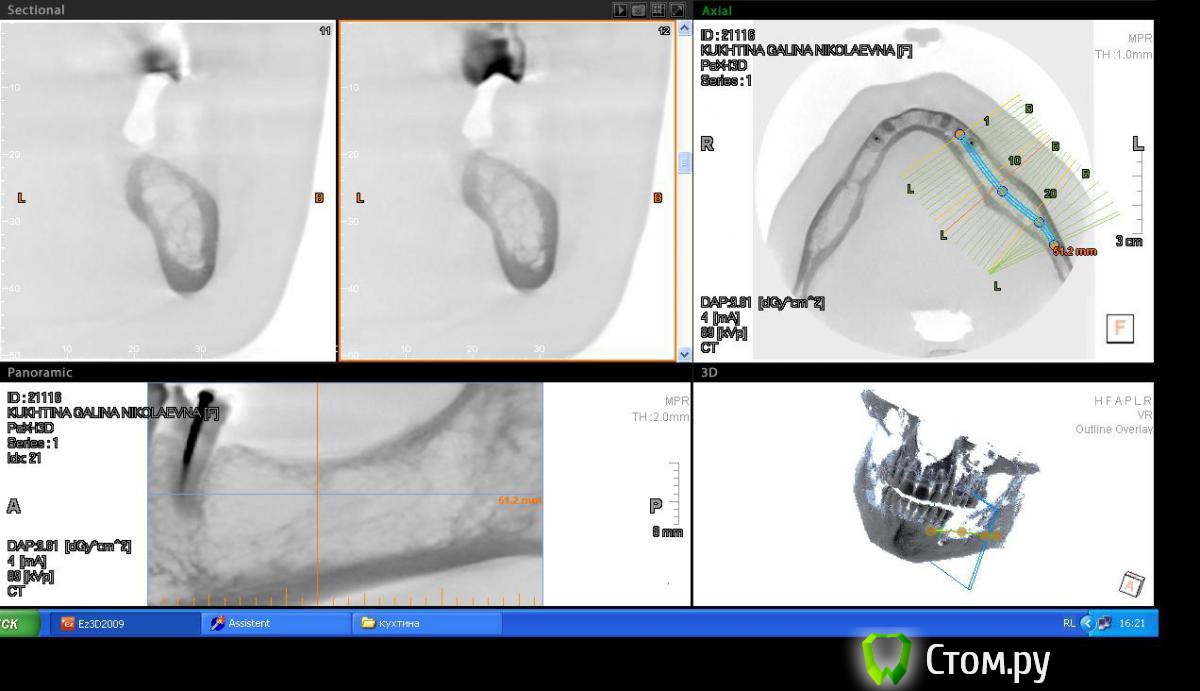

Пишем пациенту (45 лет, женщина) план ортопедического лечения, возможно с имплантами, возможно нет, пока думаем.

привлек внимание беззубый участок 36,37 зубов, уж очень большая лакуна получается, как вы думаете, онкология возможна или просто структура кости такая.

Если структура такова (склоняюсь к этому варианту, основываясь на отсутствии клиники, по контрастности на снимке, не отягощенн. анамнез), то как считаете, первичной стабильности имплантата добьемся за счет кортикалки? Или лучше в подобню яму не лезть и придумать бюгель, с другой стороны нет только 5,6,7.

Во рту клиники никакой нет.На орто ничего не видно. Жалоб нет.

прикрепил снимки в инверсии, лучше видно))